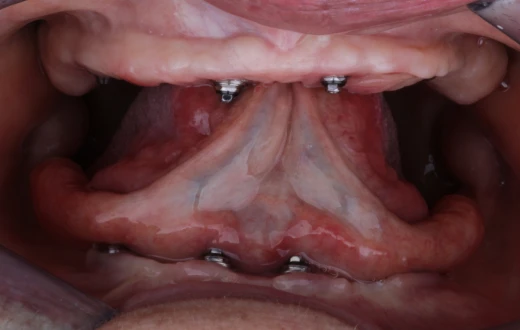

Full Arch Protocol

Your smile could be our next success story

Real transformations that inspire confidence